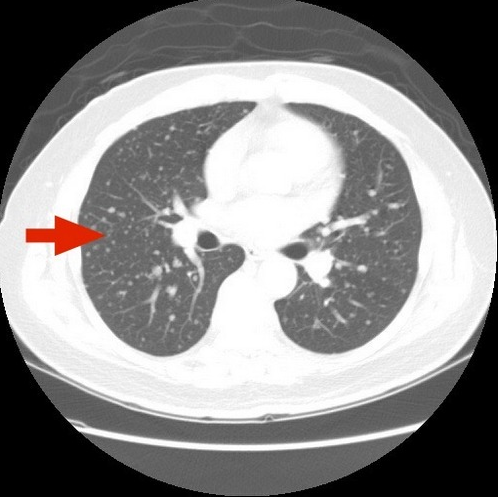

這病患在2015年發現兩側甲狀腺腫大,曾接受細針穿刺細胞學檢查,因病理報告發現細胞量不足無法確定診斷也未再接受相關檢查,直到2019年,花蓮慈院骨科陳英和醫師發現病人右大腿股骨頭、骨盆和胸骨等有多處骨質溶解的病灶,兩側肺部也有許多米粒狀小病灶。右大腿股骨頭手術後,診斷出患有轉移性濾泡甲狀腺癌,當時確定癌細胞已擴散到骨骼和肺部等處。

後因新冠疫情,病患無法再北上接受放射碘治療,由陳華宗醫師幫他申請健保給付的標靶藥物 (lenvatinib),使用兩個月後,肺部電腦斷層檢查顯示米粒狀轉移病灶已全消失。後續胸椎磁振造影追蹤也顯示胸椎骨溶及後壓現象明顯改善。陳華宗醫師提到,經數年治療,至今未發現肺部有再犯現象。標靶藥物治療過程期間病患曾出現高血壓、腹泄、體重減輕等藥物副作用,經調整藥量以上症狀也獲改善。

左圖:電腦斷層顯示,兩肺一度出現瀰漫性轉移病灶。(陳華宗醫師提供)